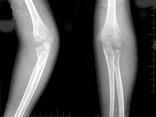

问题 女,6岁,外伤后左肘部肿痛,活动受限,外髁局部压痛,X线摄片如图,最可能的诊断是?(?)

选项 A.左肱骨小头骨骺损伤 B.左肱骨髁上骨折 C.左肱骨外上髁骨骺损伤 D.左肱骨内髁骨骺损伤 E.左肱骨外髁骨骺损伤

答案 E